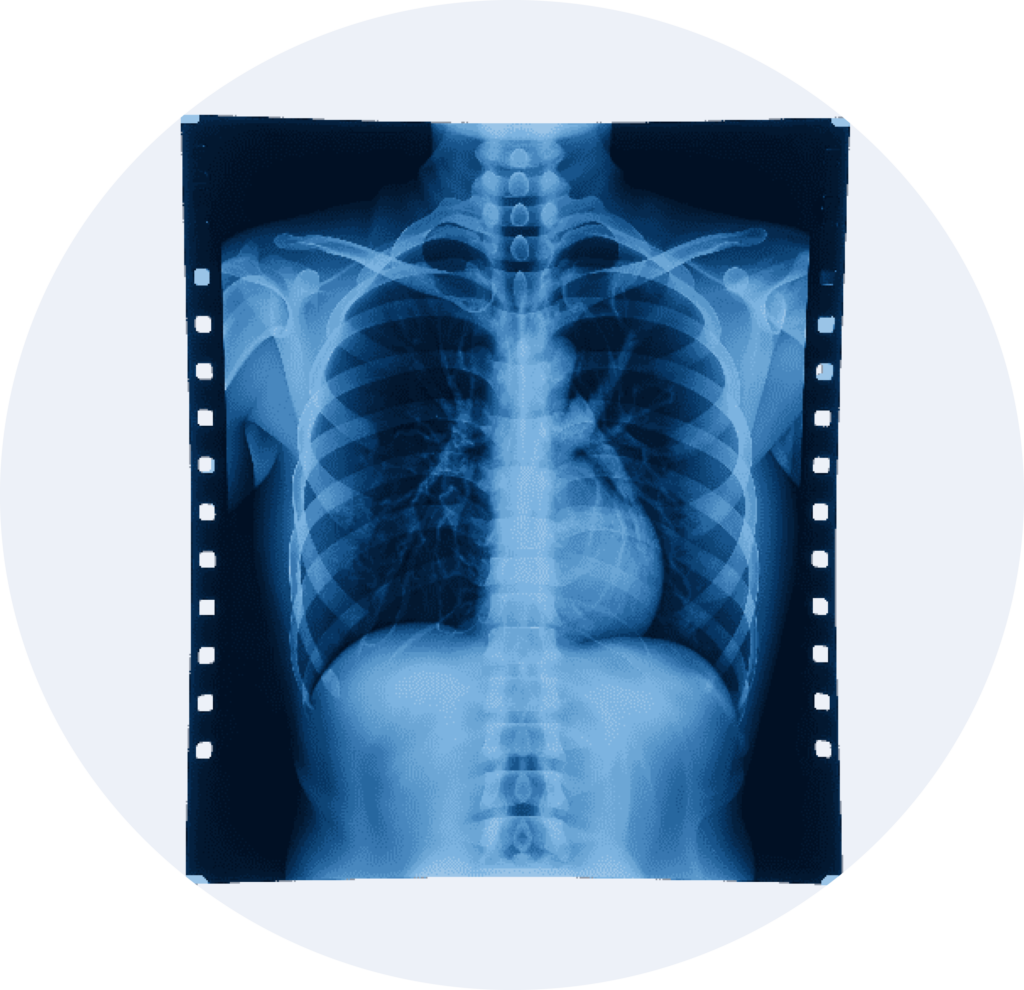

Chest X-ray image on film used for diagnostic radiology